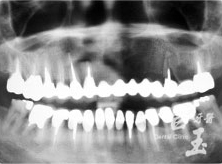

治療後